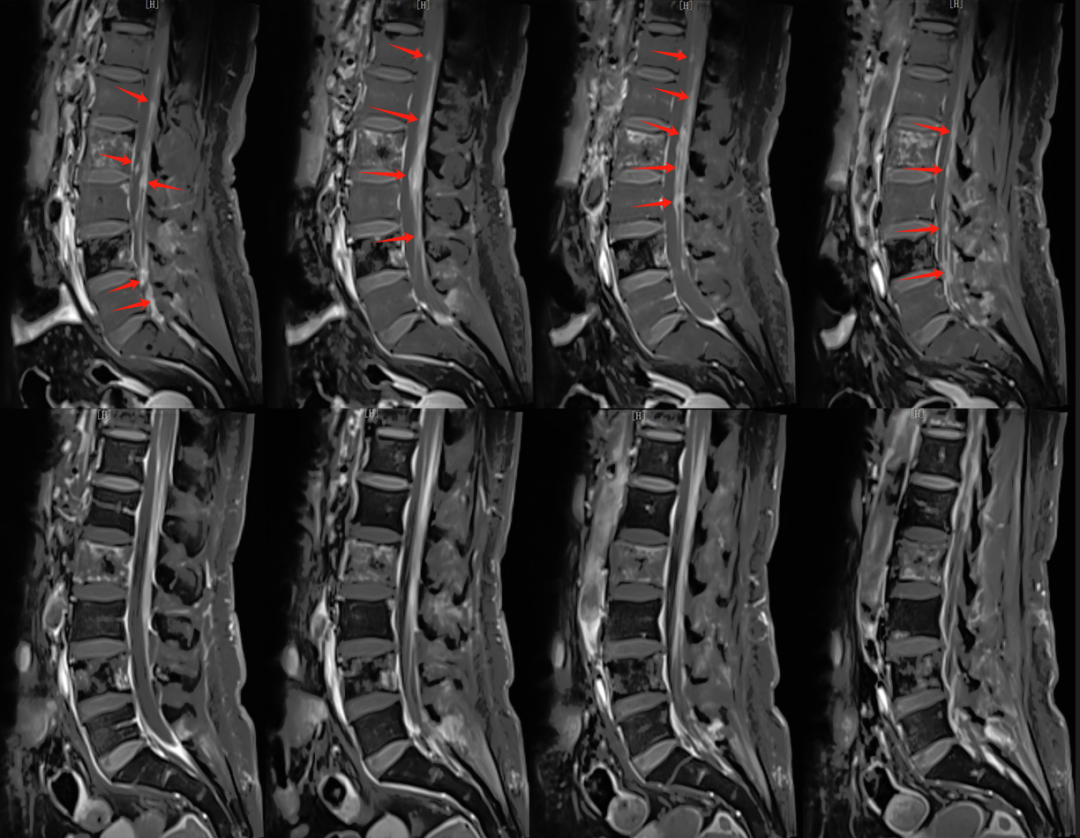

【學科風采】乳腺癌患者千里求醫(yī),成功治療多發(fā)腦轉移瘤、脊髓轉移、腦膜轉移、椎管內多發(fā)轉移結節(jié)、肺炎及肺門轉移患者